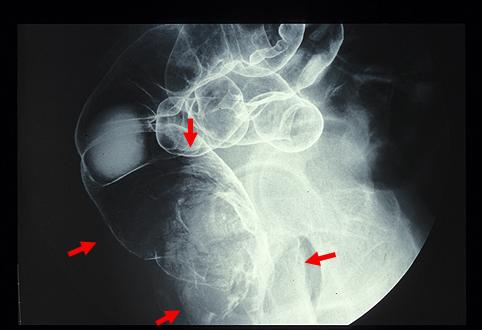

악성 비상피성종양 평활근육종 (대장)

전형적인 형태를 보인 직장의 평활근육종(GIST)

악성 비상피성종양/평활근육종

대장/직장

X-P

1형(종괴형)/

40이상

ss(a1)